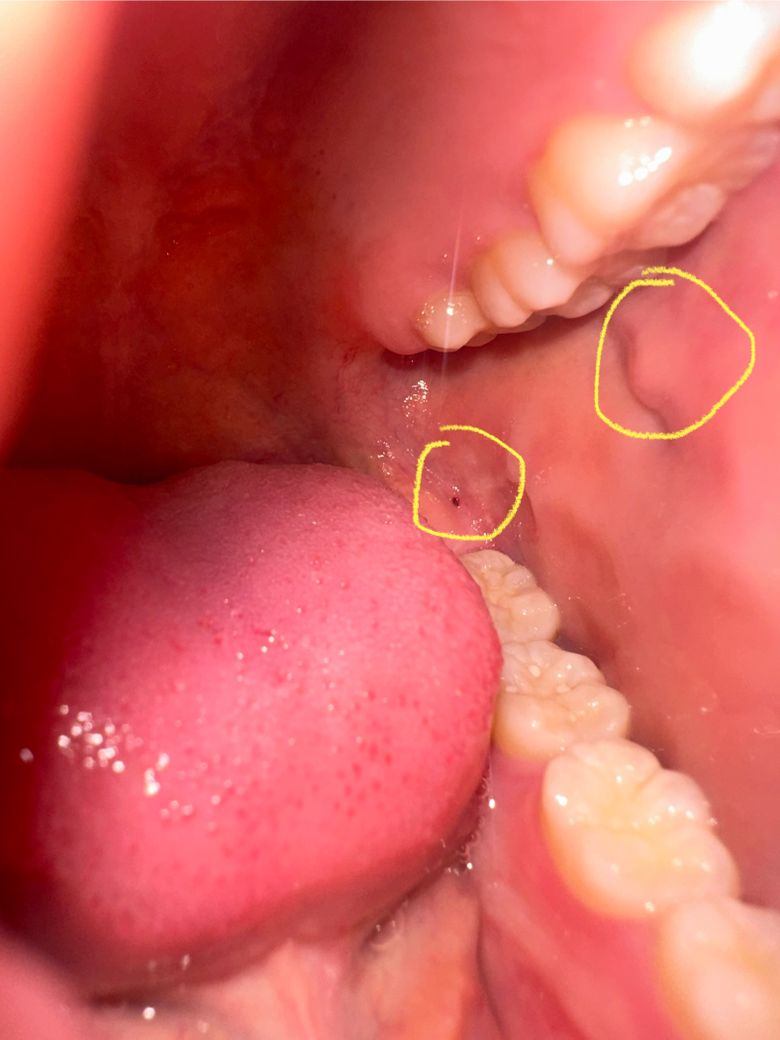

사진에 노란색 동그라미 친 부위에 볼 안쪽 살이 돌기처럼 튀어나와 있고, 어금니 뒷쪽에 피 고였을 때 생기는 것처럼 보이는 점이 있습니다 둘 다 통증은 따로 없어요 오늘 발견해서 정확히 언제부터 있었는지는 모르겠습니다

혹시 원인이 무엇일까요? 구강암일 확률은 얼마나 되나요?

구강암일 확률은 거의 없어보입니다. 해당 사진 상에서는 점막이 씹히면서 부은 것 같습니다.

동일한 질문이 여러개라 답변도 다 동일한 점 이해 부탁드리겠습니다. 첫번째 동그라미는 stensen duct, 안쪽 빨간점은 위 쪽 사랑니에 의한 자극으로 둘 모두 문제가 될 소지는 없습니다.

아래쪽에 있는 노란색은 위쪽 사랑니로 인하여 생긴 상처로 보여집니다. 흔히 위쪽 사랑니가 있고 해당 부분이 날카로우면 이러한 것들이 자주 나타납니다. 위쪽에 보이는 것은 우리 몸에 존재하는 정상적인 타액선이며 이는 정상적인 구조물이며 암이 아닙니다.